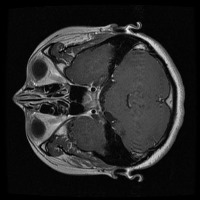

Early Detection of Brain Tumors: Use the "tesis" model to analyze MRI scans of patients proactively during routine check-ups, helping in the early identification of the presence of lesion selar or tumor hipofisario, leading to timely and potentially life-saving interventions.

Assisting in Treatment Planning: Oncologists and neurosurgeons can use the "tesis" model to study the location, size, and class of a patient's tumor. This helps in determining the best treatment options and surgical approaches, ultimately improving patient outcomes.

Medical Education and Training: Incorporate the "tesis" model in medical school curricula and professional trainings aimed at educating future doctors and radiologists about the identification and treatment of lesion selar and tumor hipofisario.

Research Tool for Cancer Studies: The "tesis" model can serve as a tool for researchers working on experimental treatments or clinical trials focused on lesion selar and tumor hipofisario. By identifying tumor classes efficiently and consistently, the model can help researchers compare treatment efficacy and study tumor progression over time.

Second Opinion Provider: Medical professionals can use the "tesis" model to double-check their own findings when analyzing brain MRI scans. This can reduce the likelihood of diagnostic errors and help confirm the presence of lesion selar or tumor hipofisario, resulting in more accurate decision-making.